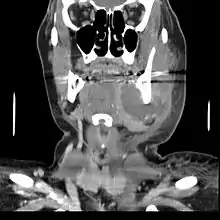

إذا تركت بدون علاج قد يصبح الخراج كبيرًا بشكل كافٍ ليثقب العظم ويمتد إلى الأنسجة الليفية فيتحة ل إلى التهاب العظم والنقي (osteomyelitis) والتهاب الهلل (cellulitis).من هناك يتبع الطريق الأقل مقاومة وينتشر إما داخليًا أو خارجيًا. مسار العدوى يتأثر بعوامل عديدة مثل موقع السن المصاب وسمك العظم، العضلات وروابط اللفائف.